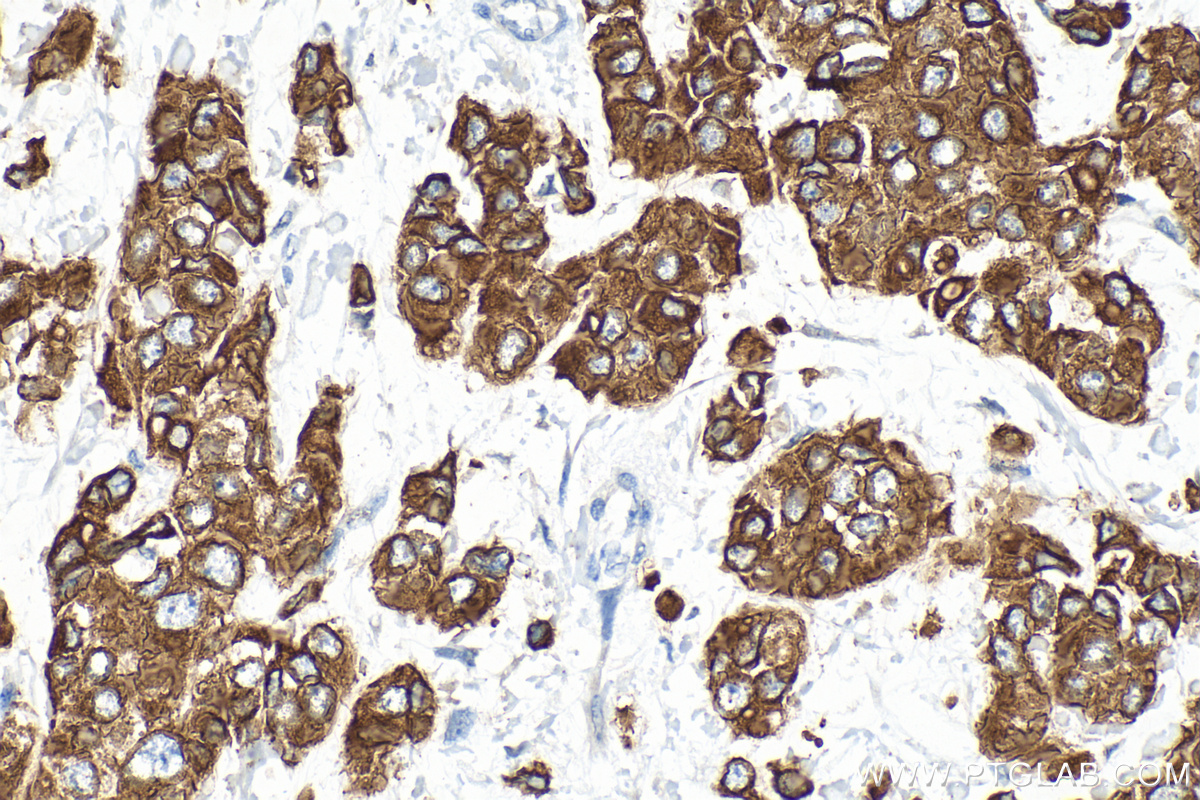

| Positive IHC detected in | human colon tissue, human breast cancer tissue, human brown disease, human cervical cancer tissue, human liver cancer tissue, human lung cancer tissue, human thyroid cancer tissue, mouse colon tissue, rat colon tissue Note: suggested antigen retrieval with TE buffer pH 9.0; (*) Alternatively, antigen retrieval may be performed with citrate buffer pH 6.0 |

| Immunohistochemistry (IHC) | IHC : 1:150-1:600 |

14965-1-AP targets Cytokeratin 19 in WB, IHC, IF/ICC, IF-Fro, ELISA applications and shows reactivity with human, mouse, rat samples.

Cytokeratin 19 (CK19 or KRT19) is a type I (acidic) cytokeratin. It is an intermediate filament protein providing structural rigidity and multipurpose scaffolds in epithelial cells. CK19 is often overexpressed in various cancers (e.g., hepatocellular carcinoma [HCC], pancreatic adenocarcinoma, lung cancer) and serves as a biomarker for hepatic progenitor cells (HPCs) associated with poor prognosis in HCC patients . Additionally, CK19 expression is common in pancreatic and gastrointestinal adenocarcinomasand has been studied as a potential diagnostic and prognostic marker for pancreatic neuroendocrine tumors (PNETs), where positive CK19 expression correlates with poor prognosis. Serum CK19 fragments (e.g., CYFRA 21-1, CK19-2G2) have been investigated as tumor markers for lung and breast cancer, with preoperative levels associated with metastasis and survival. This antibody, generated against full length KRT19 protein, also recognizes KRT17, another type I keratin homologous to KRT19.